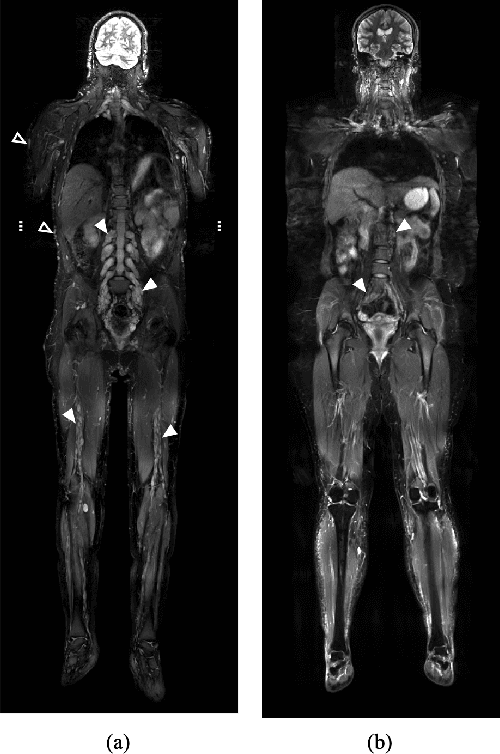

Abstract:Neurofibromatosis Type 1 is a genetic disorder characterized by the development of neurofibromas (NFs), which exhibit significant variability in size, morphology, and anatomical location. Accurate and automated segmentation of these tumors in whole-body magnetic resonance imaging (WB-MRI) is crucial to assess tumor burden and monitor disease progression. In this study, we present and analyze a fully automated pipeline for NF segmentation in fat-suppressed T2-weighted WB-MRI, consisting of three stages: anatomy segmentation, NF segmentation, and tumor candidate classification. In the first stage, we use the MRSegmentator model to generate an anatomy segmentation mask, extended with a high-risk zone for NFs. This mask is concatenated with the input image as anatomical context information for NF segmentation. The second stage employs an ensemble of 3D anisotropic anatomy-informed U-Nets to produce an NF segmentation confidence mask. In the final stage, tumor candidates are extracted from the confidence mask and classified based on radiomic features, distinguishing tumors from non-tumor regions and reducing false positives. We evaluate the proposed pipeline on three test sets representing different conditions: in-domain data (test set 1), varying imaging protocols and field strength (test set 2), and low tumor burden cases (test set 3). Experimental results show a 68% improvement in per-scan Dice Similarity Coefficient (DSC), a 21% increase in per-tumor DSC, and a two-fold improvement in F1 score for tumor detection in high tumor burden cases by integrating anatomy information. The method is integrated into the 3D Slicer platform for practical clinical use, with the code publicly accessible.